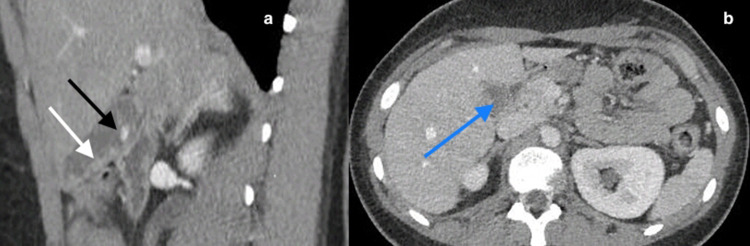

Case report: A 21-year-old diabetic woman presented with one day of nausea, vomiting, and persistent right upper quadrant abdominal pain. Ultrasonography and computed tomography scan revealed an enlarged gallbladder with biliary sludge and a single gallstone. A preoperative diagnosis of acute cholecystitis was made, and cholecystectomy was performed. Histopathological examination confirmed acute cholecystitis and demonstrated numerous filamentous, gram-positive bacteria, consistent with actinomycosis. Following 6 months of penicillin therapy, the patient remains well with no clinical or radiological evidence of recurrence.